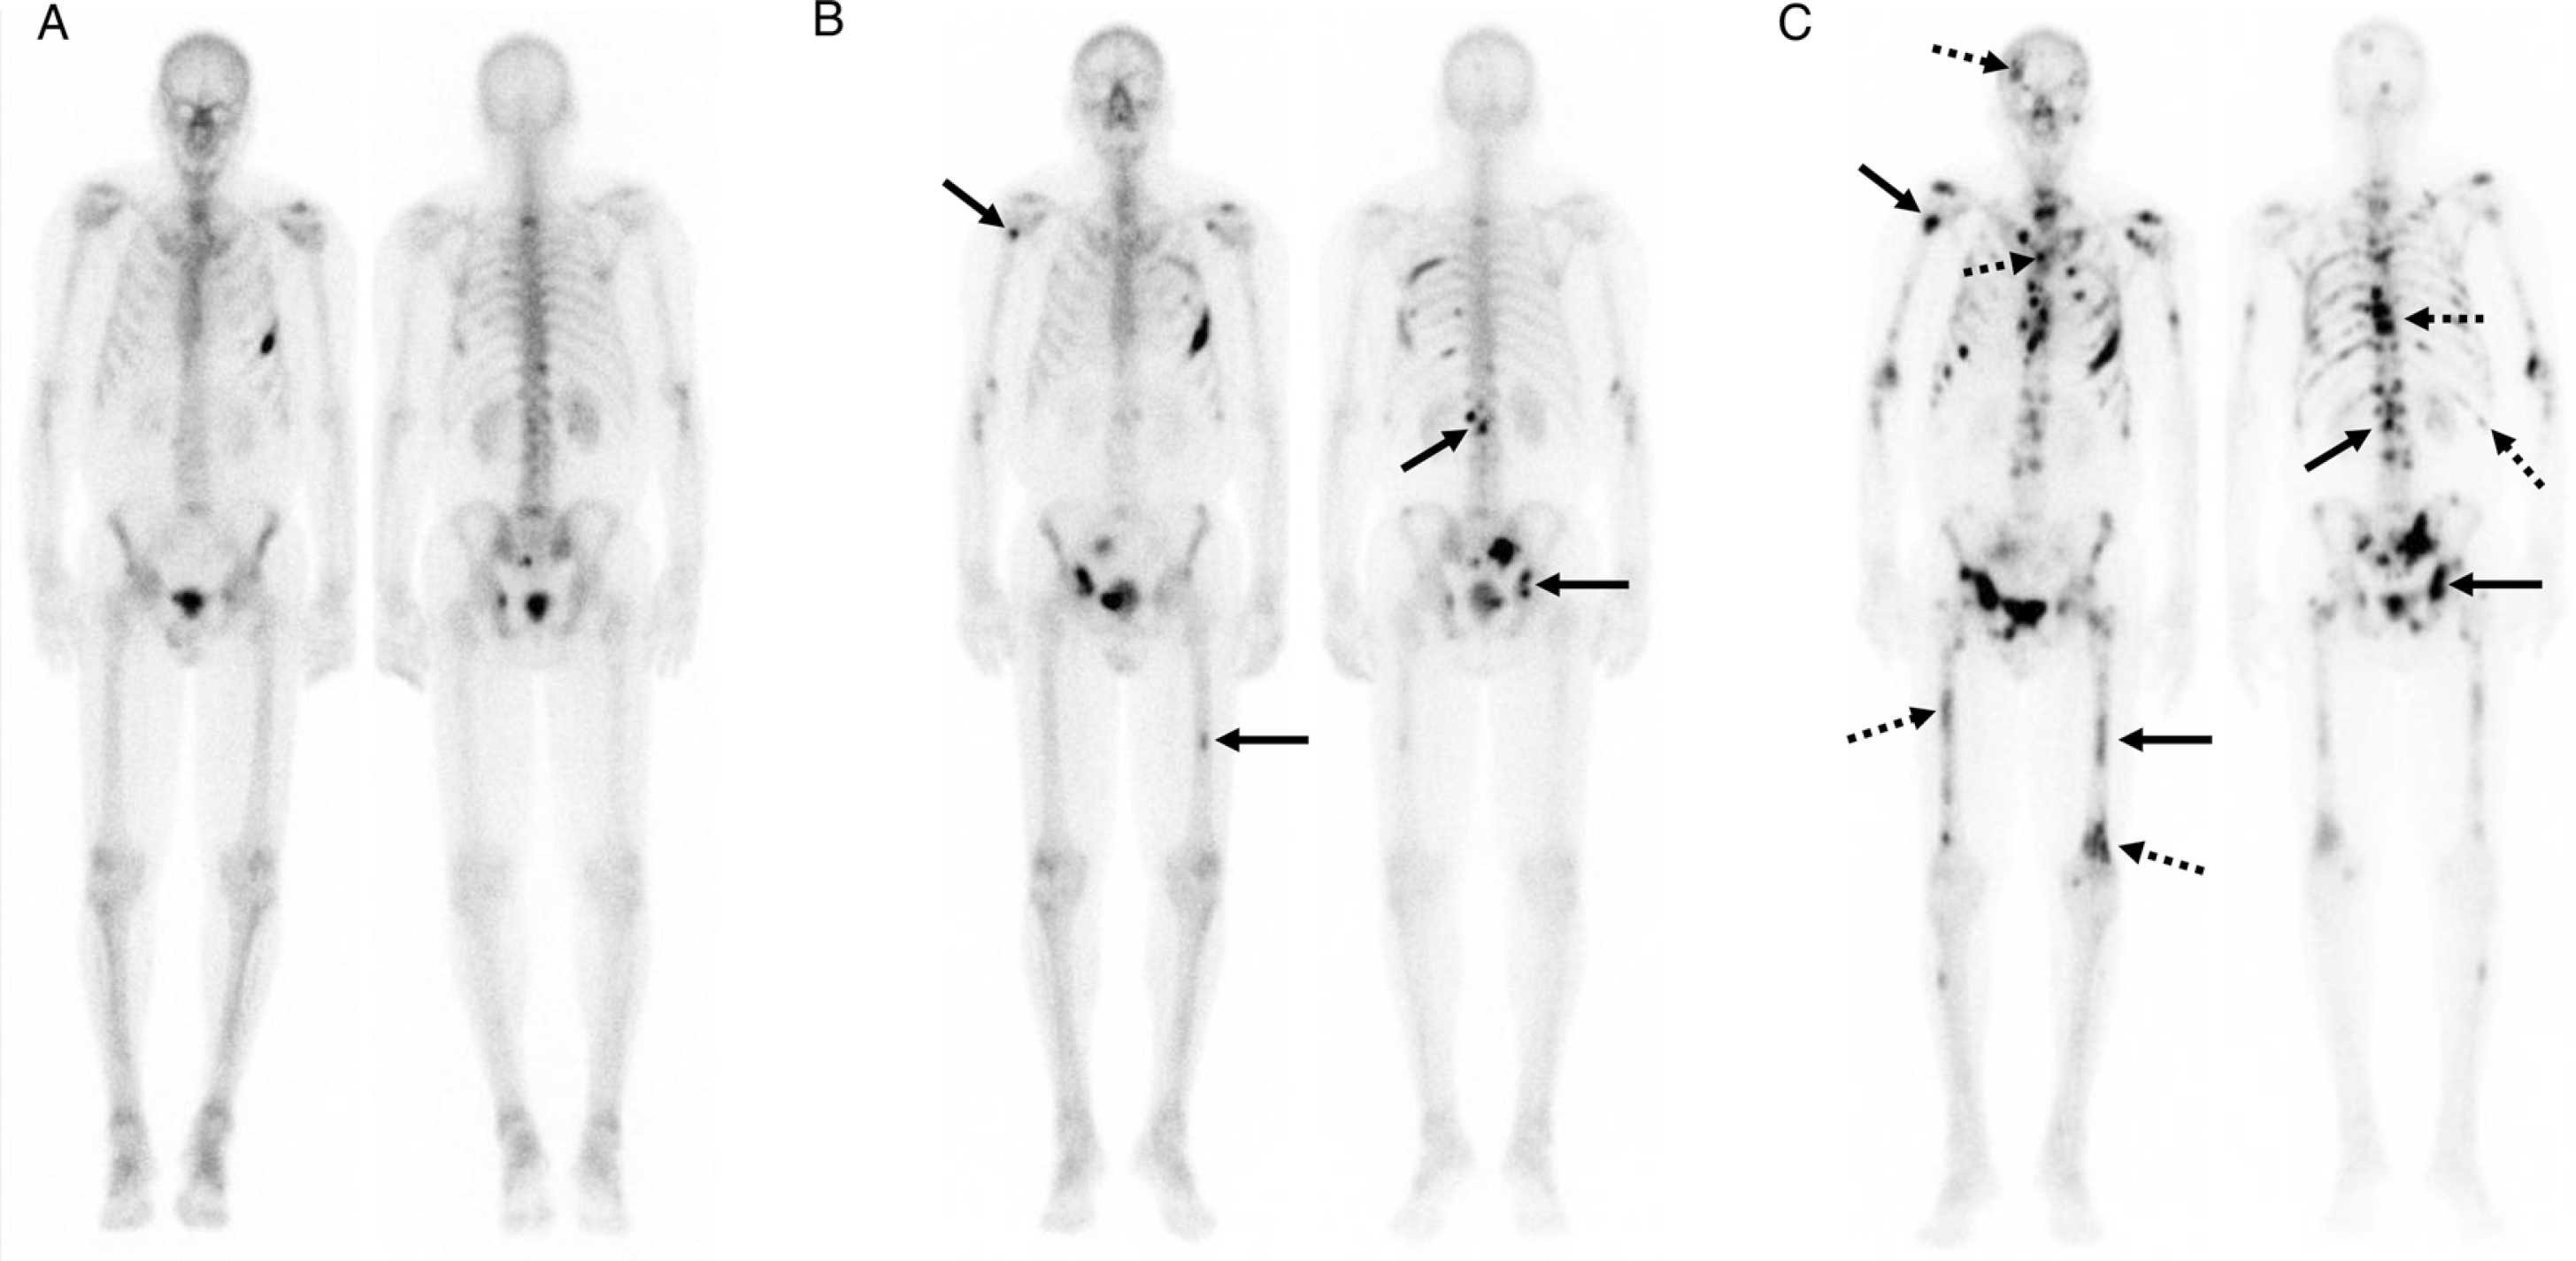

Interventional oncology update

June 20, 2022. Author(s): Alex Newbury, Chantal M. Ferguson, Daniel Alvarez Valero, Roberto Kutcher-Diaz, Lacey J. McIntosh, Ara Karamanian, Aaron Harman. Source: European journal of radiology open